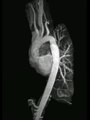

Cardiac MRI leads to better diagnosis

Cardiac MRI - Aorta angiogram with coarctation